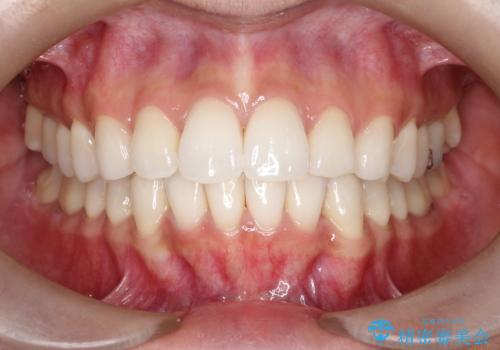

前歯の突出を防ぎながらガタつきを解消。上下左右4番抜歯による審美ワイヤー矯正

担当医 河口智英